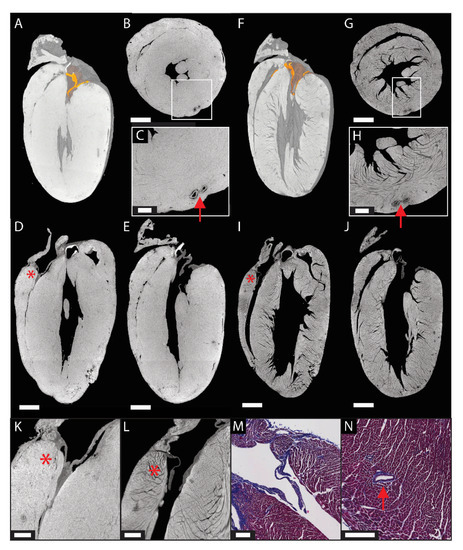

- Novo Matos, J.; Garcia-Canadilla, P.; Simcock, I.C.; Hutchinson, J.C.; Dobromylskyj, M.; Guy, A.; Arthurs, O.J.; Cook, A.C.; Luis Fuentes, V. Micro-Computed Tomography (Micro-CT) for the Assessment of Myocardial Disarray, Fibrosis and Ventricular Mass in a Feline Model of Hypertrophic Cardiomyopathy. Sci. Rep. 2020, 10, 20169. [Google Scholar] [CrossRef] [PubMed]